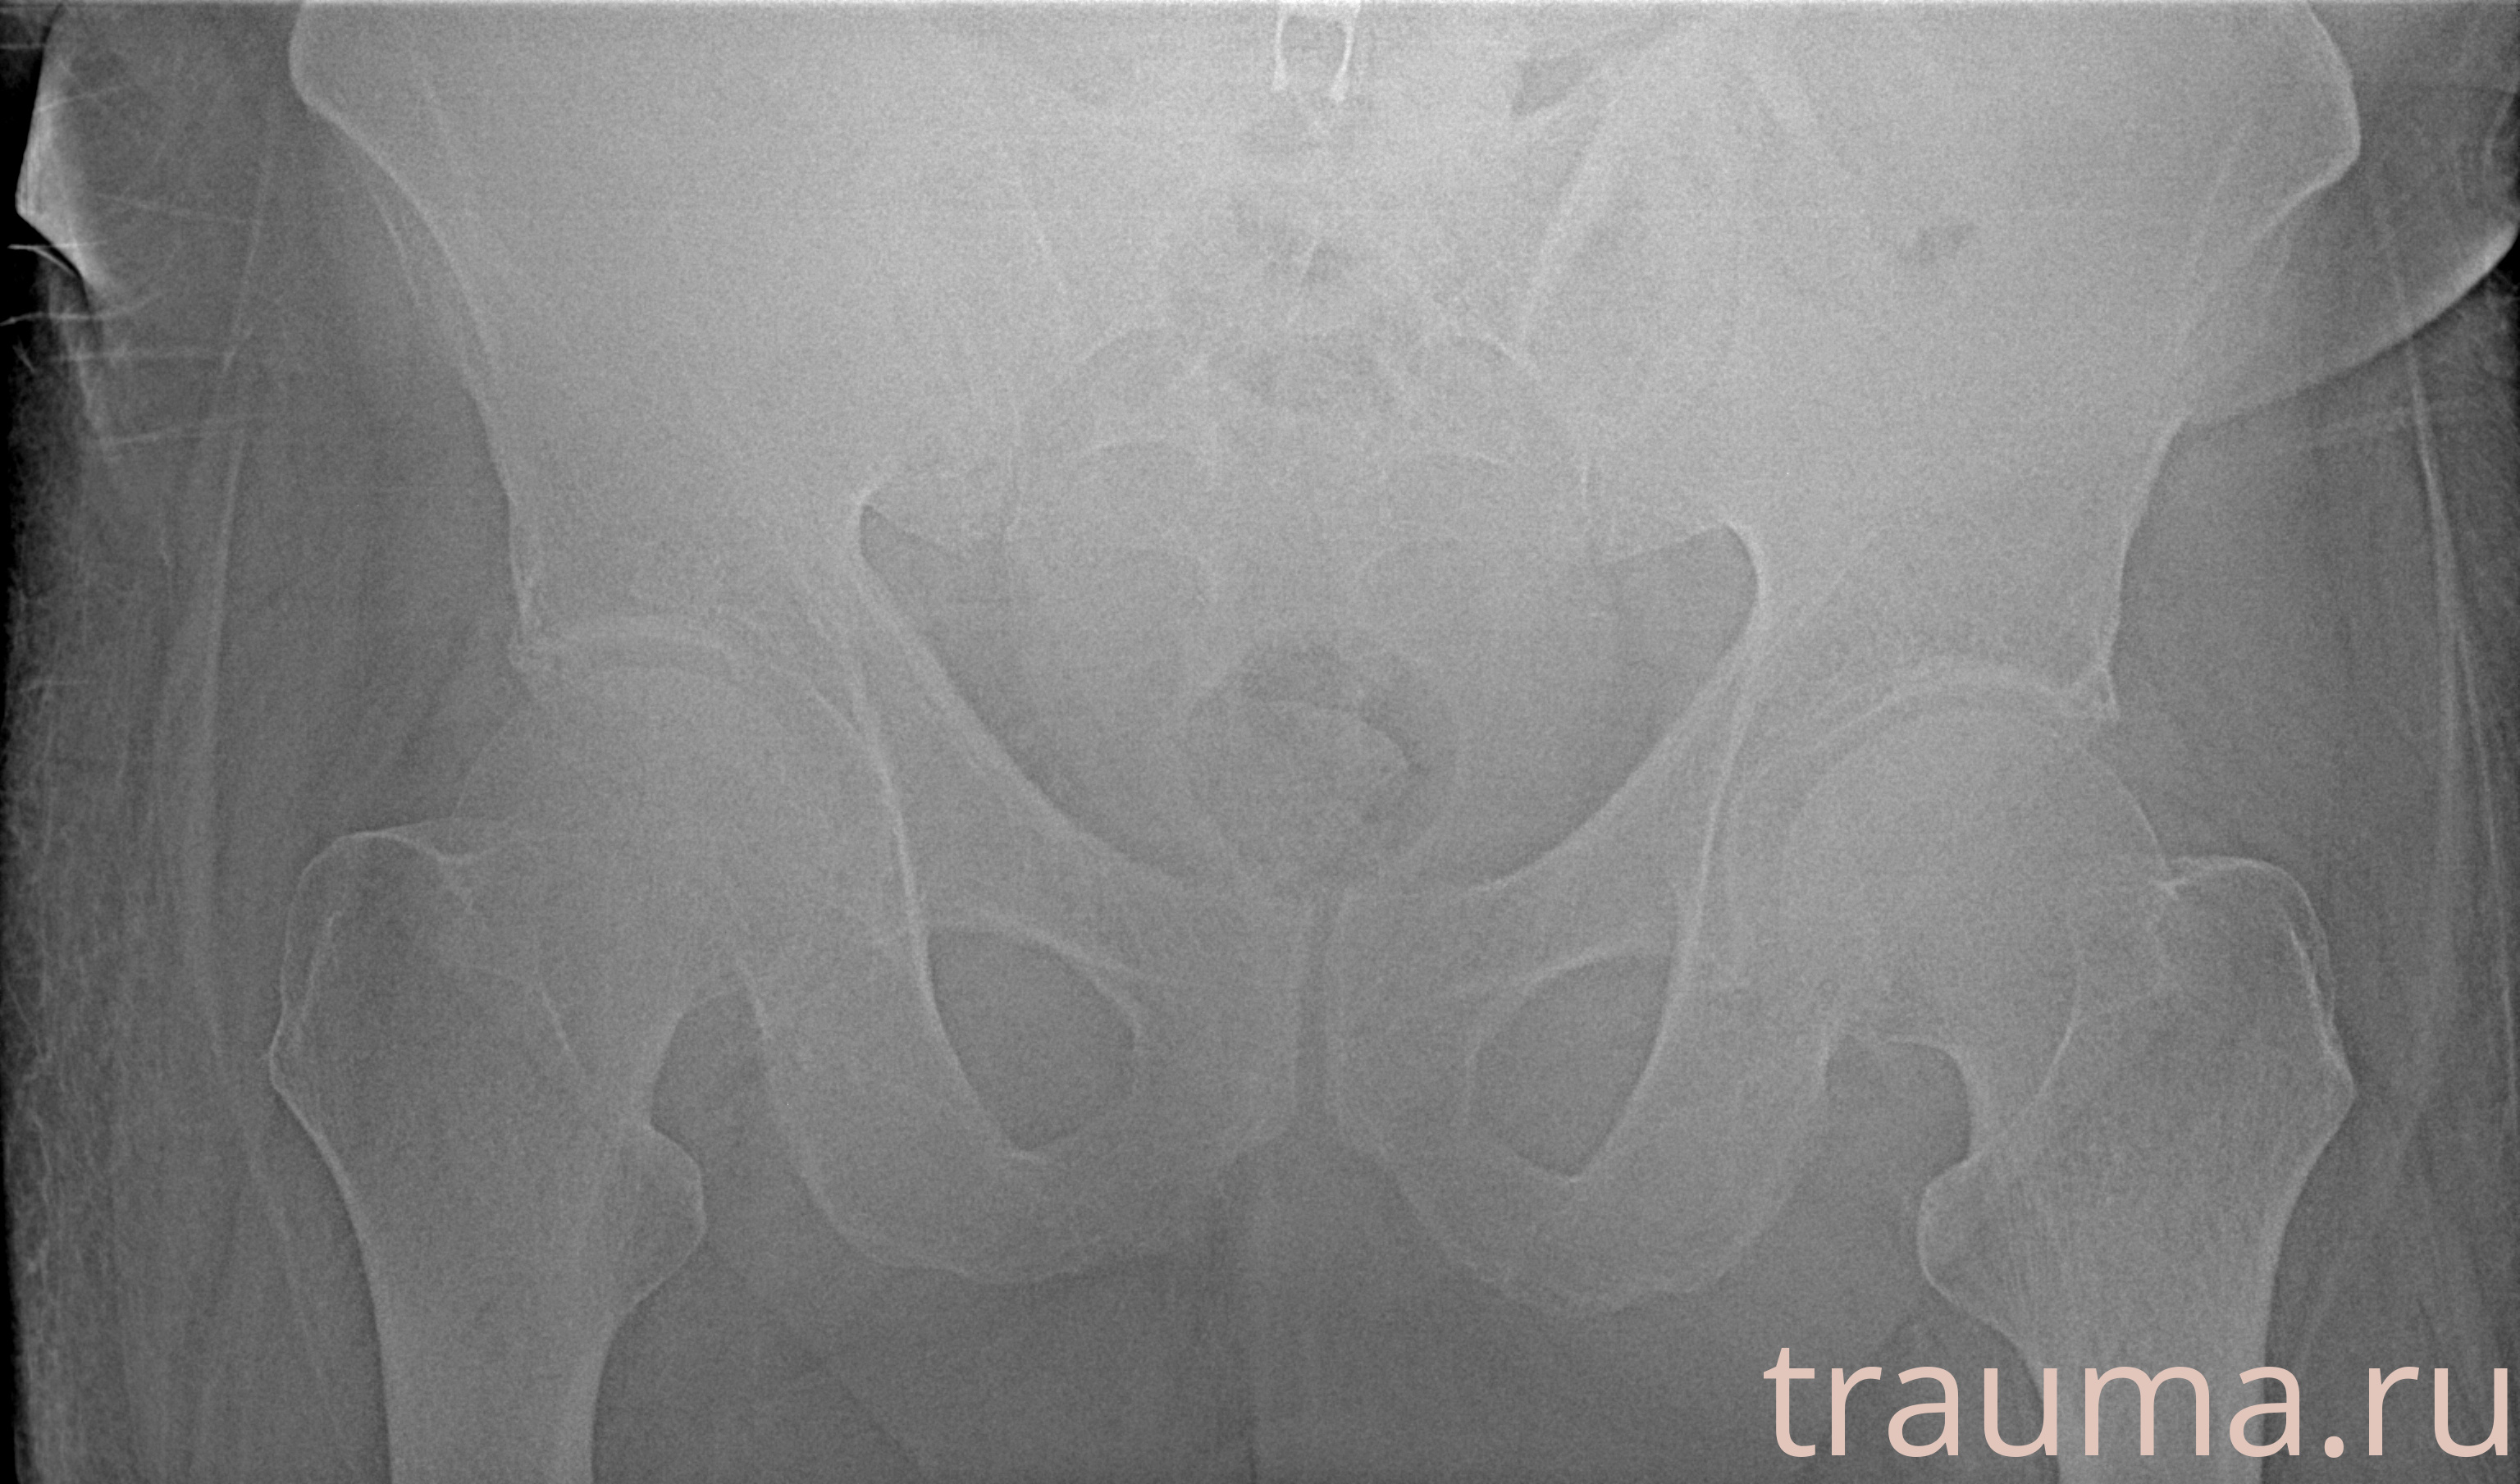

Первая помощь при переломе шейки бедра

Рентген на дому: по вашему адресу приезжает врач-рентгенолог, травматолог-ортопед с мобильным рентгеновским аппаратом, проводит диагностику травмы или заболевания, делает необходимые рентгенограммы, дает рекомендации по дальнейшему лечению. Получить качественные снимки в домашних условиях возможно благодаря уникальной методике, разработанной МосРентген Центром для института  Склифосовского